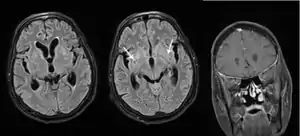

La infección ocurre por inhalación del microorganismo hasta los alveolos. Si bien al principio puede producir síntomas pulmonares leves, luego se diseminan por vía hematógena hasta llegar al SNC, una vez en el SNC, la escasez de anticuerpos, elementos del complemento y de glóbulos blancos permite que los microorganismos puedan florecer. La inflamación es el elemento característico de la enfermedad e incrementa la permeabilidad de la barrera hematoencefálica causando edema, esta no es producto directo de la infección, si no que es el mismo sistema nervioso que está reaccionando a la presencia del microorganismo invasor. El edema causa aumento de la presión intracraneal, haciendo que sea más difícil para la sangre llegar a las neuronas cerebrales, disminuyendo así el aporte de oxígeno lo que conlleva a la muerte celular o apoptosis.

- Hidrocefalia, con los signos y síntomas correspondientes a esta.